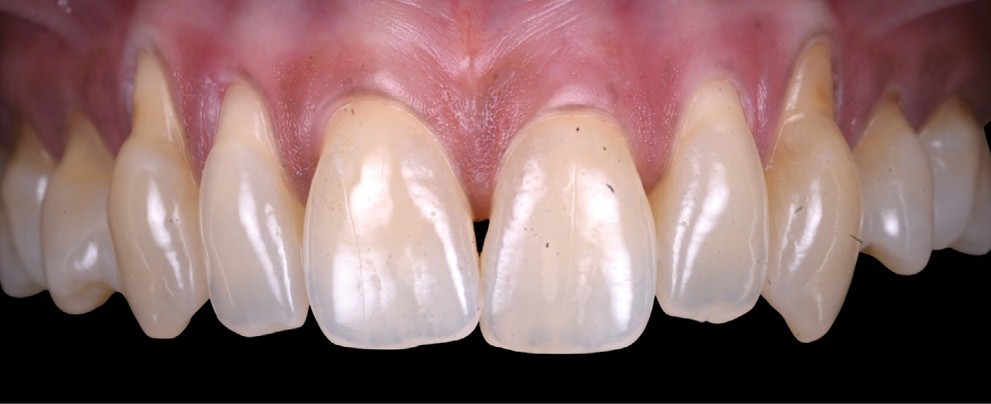

L’examen clinique révèle des récessions gingivales généralisées au maxillaire (fig. 1), de type RT1 et RT2 selon Cairo, responsables d’une hypersensibilité dentinaire marquée.